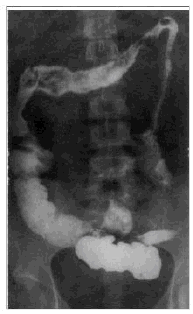

(3). 提示:入院后该患者钡餐检查如图。其钡餐检查特点有哪些

A. 病变阶段性分布

B. 钡剂涂布不良,模糊不清

C. 部分肠壁增厚明显

D. 结肠内可见许多增生结节形成小充盈缺损

E. 结肠边缘毛糙,结肠带消失

F. 管壁僵硬,呈蜡管状